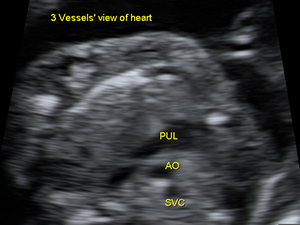

The 3 vessels’view of the fetal heart